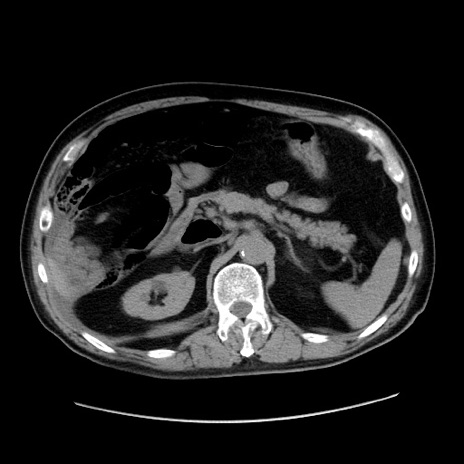

冠状断像

【症例】80歳代男性

【主訴】臍周囲痛

【現病歴】約6時間前から臍下部痛が出現。次第に腹部膨隆・背部痛も生じてきたため来院。背部痛の場所は変化しない。

【身体所見】意識清明、BT 36.3℃、BP  131/87mmHg、P 87bpm、SpO2 100%(RA)、臍周囲自発痛・圧痛あり、反跳痛なし、自発痛部位に一致して板状硬あり、腹部膨隆、腸雑音減弱、CVA tenderness両側陰性。

【データ】WBC 19600、CRP 0.33